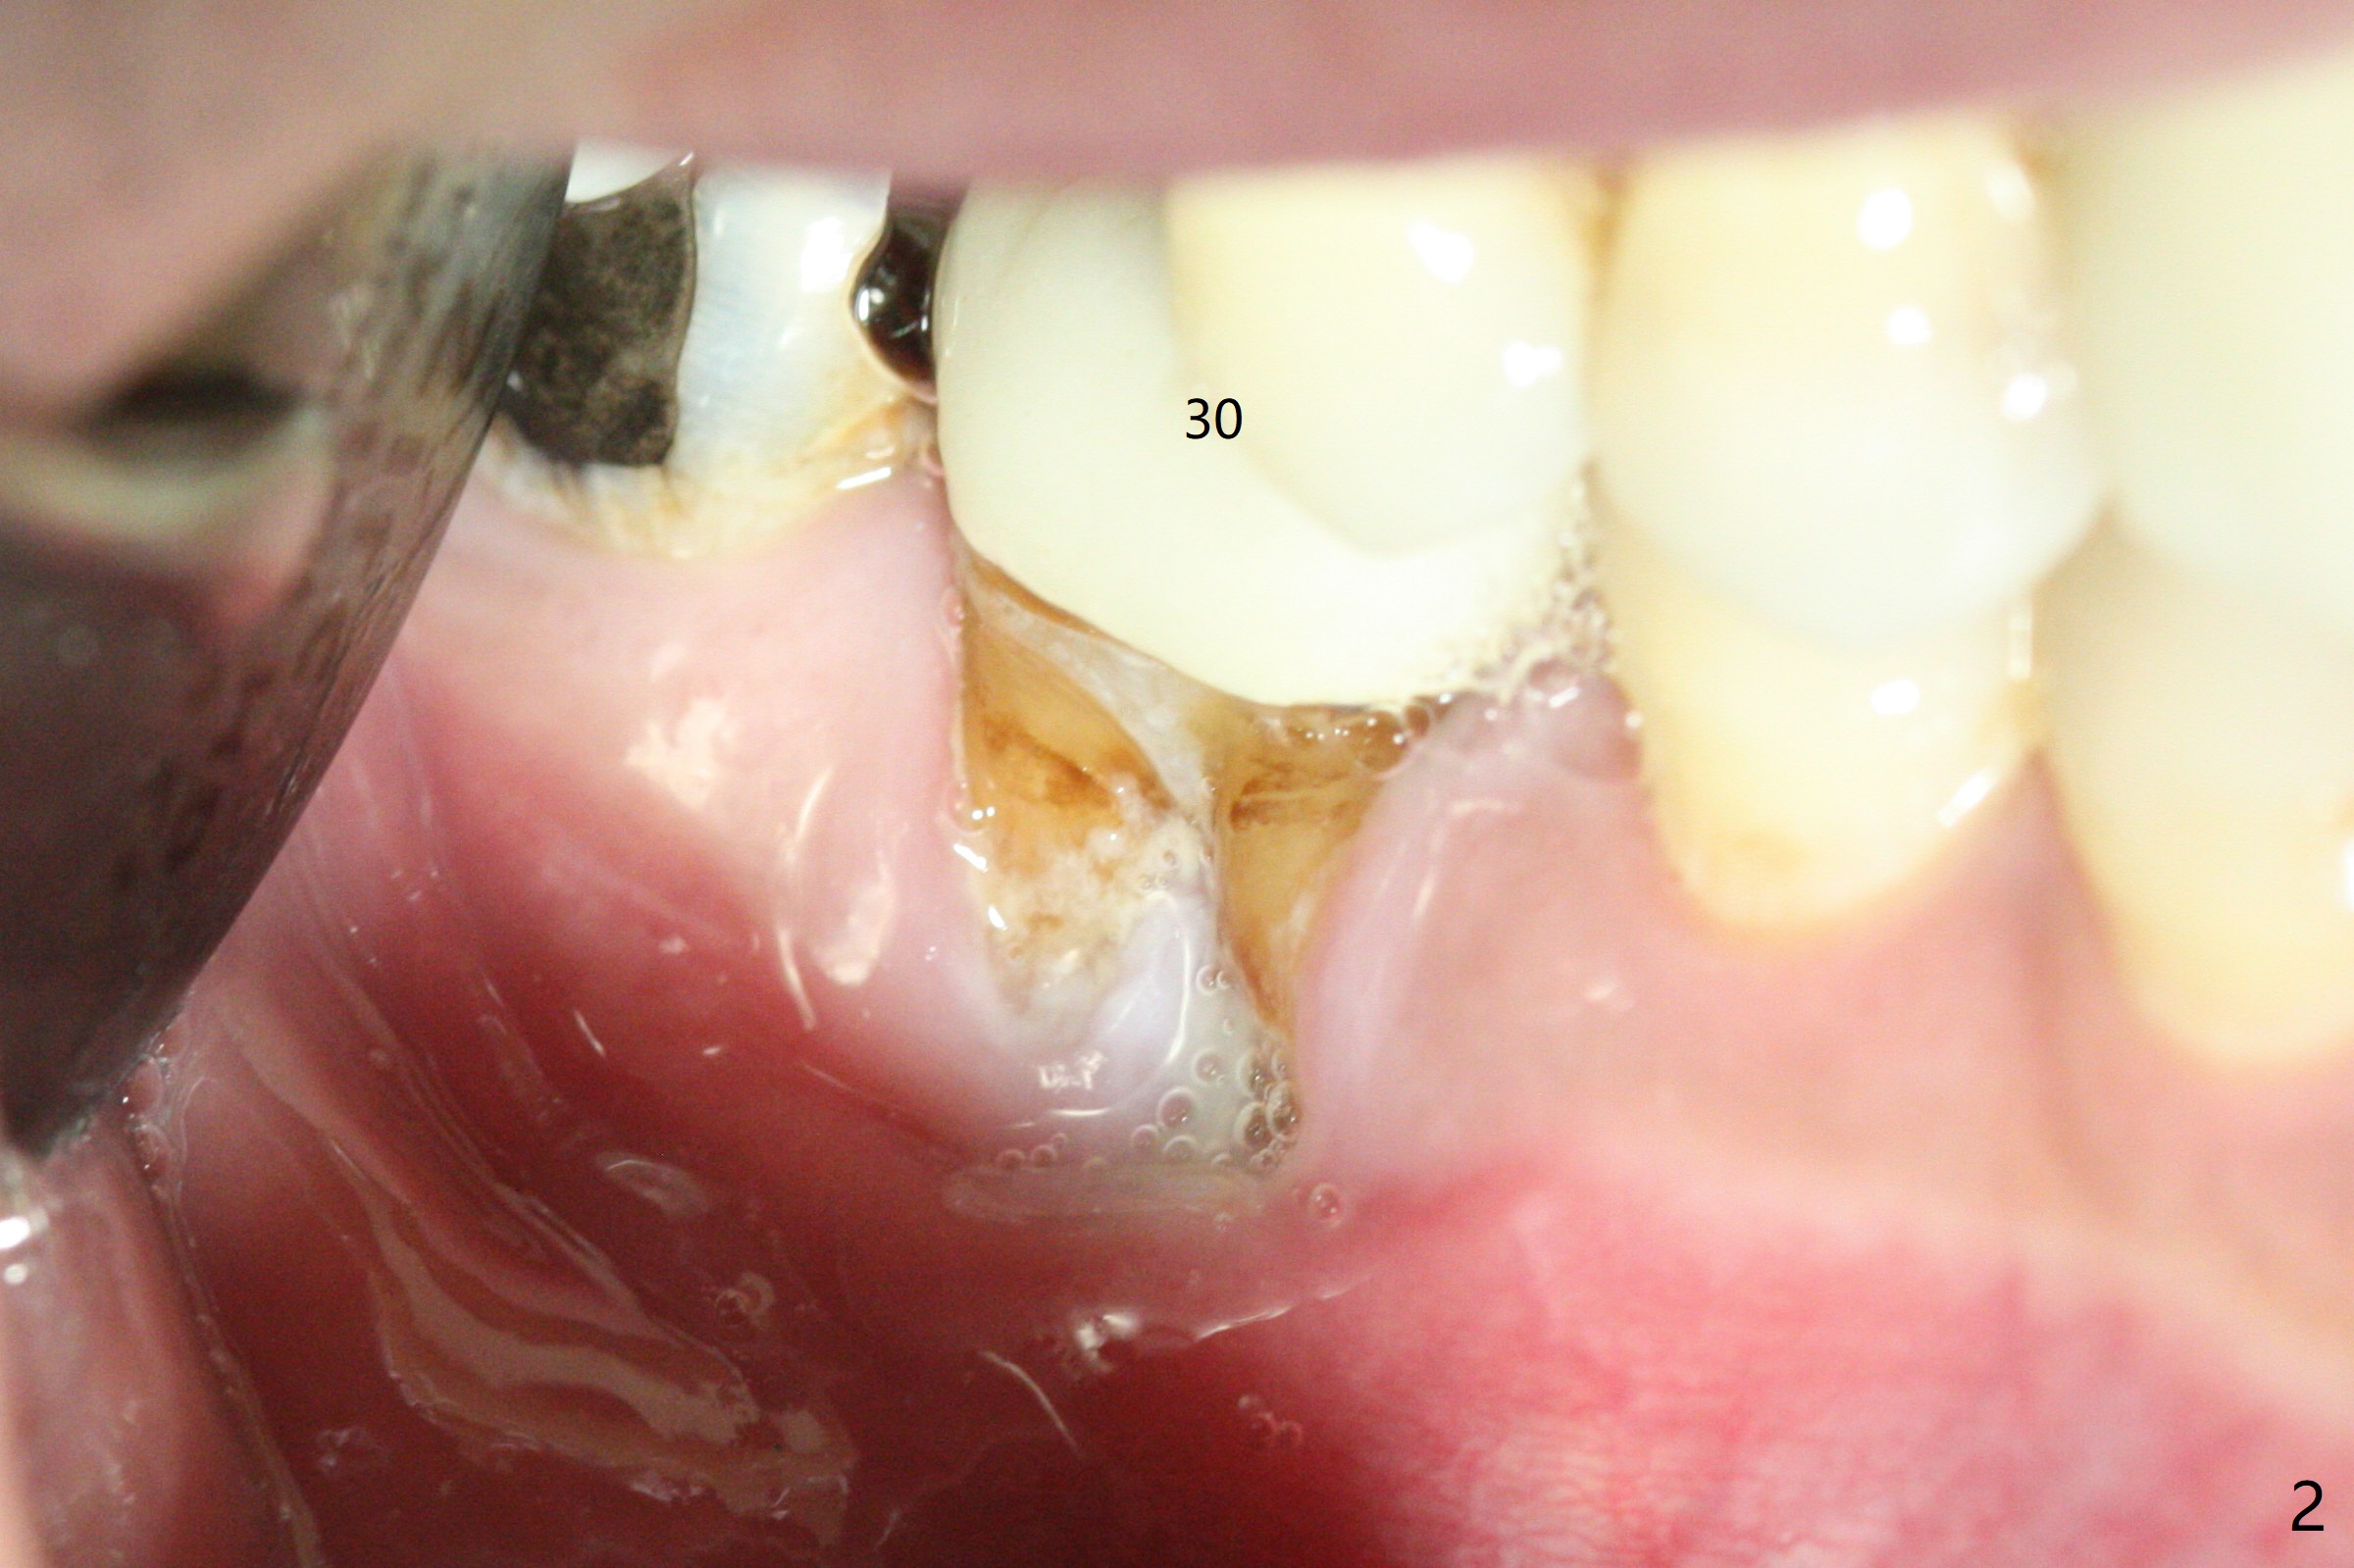

A 47-year-old man has poor dentition. The tooth #31 needs RCT, while #30 has severe PARL, especially mesial (Fig.1 M). The buccal roots are exposed (Fig.2). Between the exposed roots is the septal gingiva, which will be saved for buccal soft tissue repair (Fig.3 *). The septal gingiva will keep in place (not to be transferred) so that the recession will disappear by epithelial regrowth from the nearby gingiva (Fig.3' arrows) over the bone graft and PRF. The provisional should be fabricated to cover the soft tissue defect (Fig.3'' yellow area). In fact the mesial root fractures (Fig.4 ^), as related to the severe bony defect. There seems to be enough lingual bone to hold a 4x13 mm implant (Fig.5 green). Sticky bone (Fig.6 red circles) and PRF (blue) are to be used to repair the hard and soft tissue defects following an immediate provisional (Fig.5,6 yellow outline). Extra layer of acrylic (Fig.6 orange) will be used to cover the PRF buccally. The base of the buccal plate is thick (Fig.6 *); mesial portion appears to be denser (Fig.7 black *) than the distal one (white *). Decortication will be done if hemorrhage is insufficient. Fig.8 is a coronal section of the socket (B: buccal). Extraction (Fig.9 black area) will most likely result in a knife edge ridge. Extraction with bone graft may not fare better, as it is easy to lose the graft considering missing buccal hard and soft tissues.